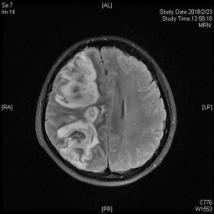

图为患者头颅MRI影像